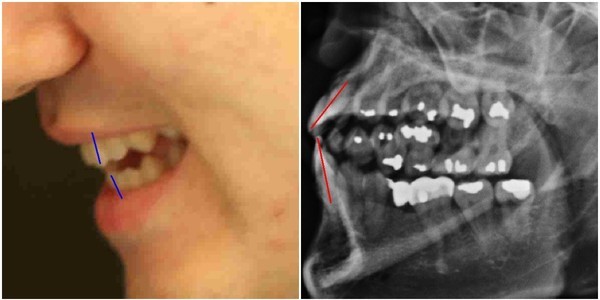

- ▲ 박주신씨 치아엑스레이와 주신씨의 치아가 보이는 실물 사진. ⓒ 뉴데일리DB

박주신씨 명의의 치아엑스레이는 이 사건 피고인들이, 주신씨 명의의 흉부엑스레이와 함께, ‘대리신검’ 혹은 ‘영상자료 바꿔치기’ 의혹의 주요 증거로 꼽고 있는 영상자료다.

주신씨가 자생병원에서 촬영한 것으로 알려진 이 치아엑스레이에 대해 피고인들이 강한 의문을 나타내는 이유는, 엑스레이 속 치아의 상태가 도저히 20대 중반 청년의 것이라고는 보기 힘들만큼 불량하기 때문이다.